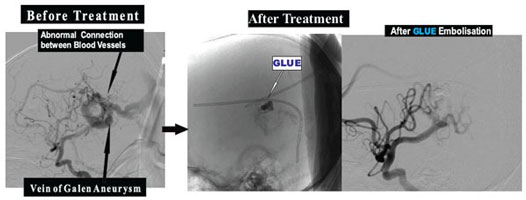

Embolisation of Vein Of Galen Aneurysmal malformation (VOGAM) :

These are abnormal Connections between Arteries and Veins in Brain causing increase in pressure in Brain Veins causing Heart Failure, Stunted Growth or Fits/ Epilepsy.

With Interventional Neuroradiological ,Without opening the Skull ; these Connections between Arteries Abnormal and Veins in Brain can be treated by technique of Glue Embolisation .

Example: 4 month old baby boy presented with Stunted Growth and large head due to Vein Of Galen Aneurysmal malformation (VOGAM). After GLUE Embolisation of Vein Of Galen Aneurysmal malformation (VOGAM), now he is growing at normal stages.